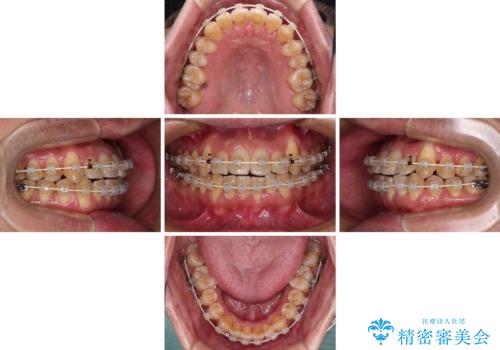

クロスバイトは、治療の過程で咬み合わせが大きく変化する期間があり、食事が取りにくくなってしまいます。

また、装置が対合歯と咬み合ってしまい、頻繁に脱落するなど、色々と面倒なことがあり、治療がスムーズに進まないことがあります。

デコボコが解消されると歯列が拡大される方向に動くため、出っ歯のような仕上がりとなることがあります。舌の突出癖を改善するトレーニングをしっかりと行っていただくことで、突出を抑制することができます。